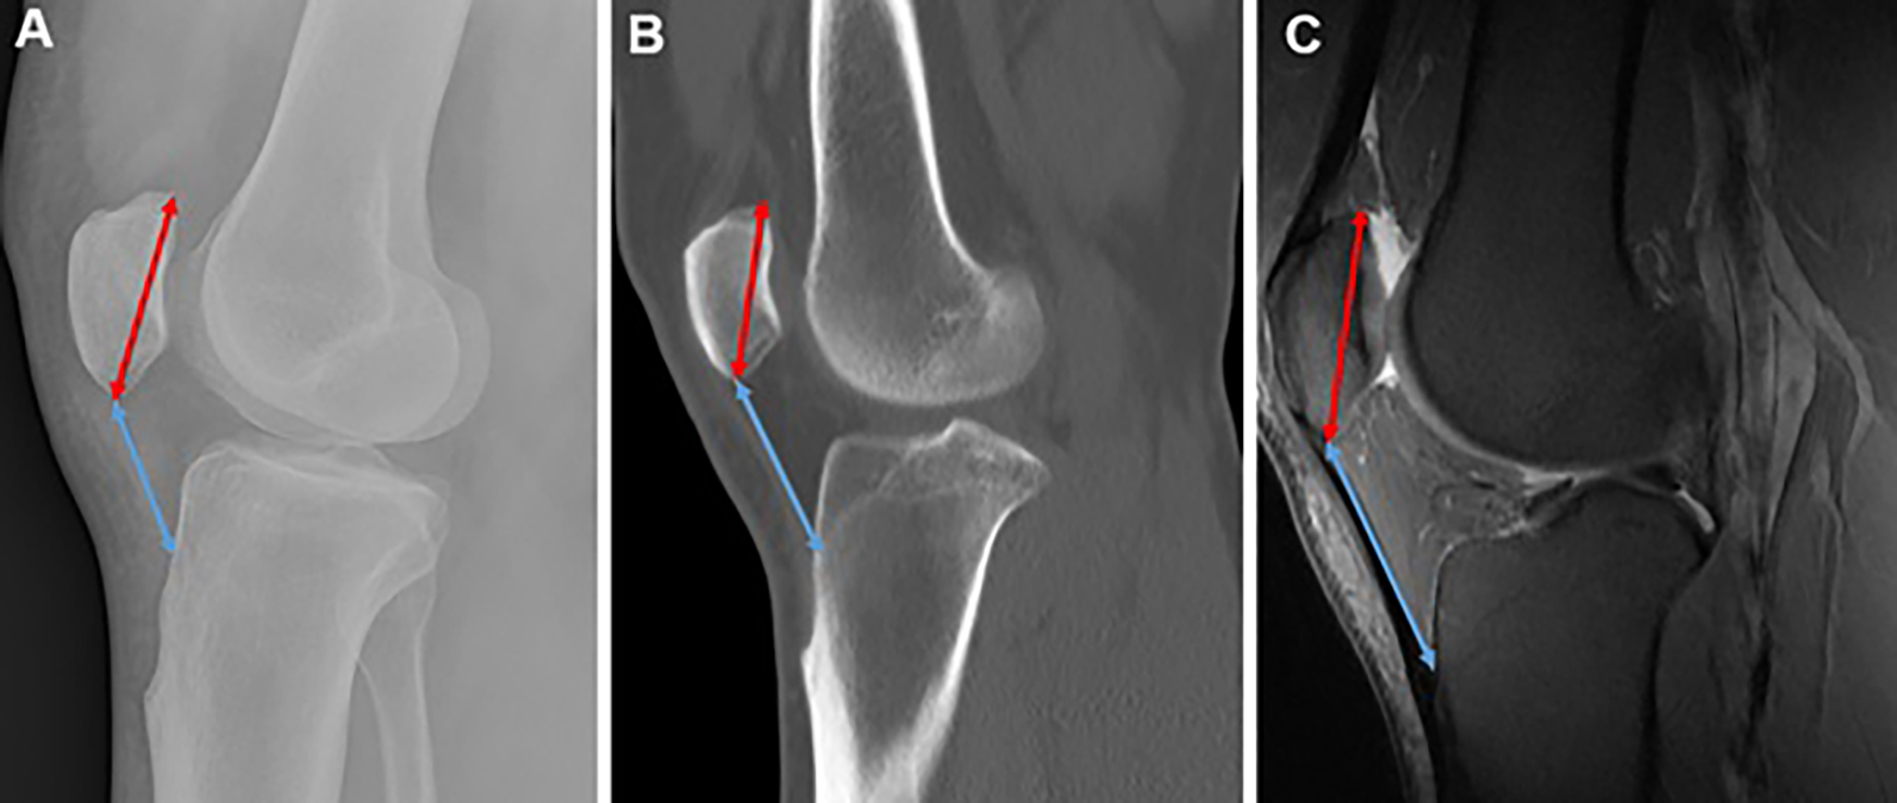

The study assessed two widely used patellar height indices: the Insall– Salvati and Blackburne–Peel ratios. For the Insall–Salvati method (Figure 2), patellar length was measured from the posterior superior articular margin to the most distal anterior tip, excluding osteophytes. The longest diagonal length was used. Tendon length was measured from the distal anterior patella to the tibial tuberosity. In cases of tendon laxity, a straight-line measurement was applied. The Insall– Salvati ratio was calculated as the tendon length divided by patellar length, providing a standardized assessment of patellar height.

Figure 2

Figure 2. CT = Computed tomography; IS = Insall–Salvati; MRI = Magnetic resonance imaging; X-Ray=Radiograph. A. Lateral radiograph depicting the IS measurements. The patellar length (red line with arrows at both ends) is measured from the tip of the posterior articular margin to the distal anterior tip of the patella. The patellar tendon length (blue line with arrows at both ends) is obtained by measuring from the distal anterior tip of the patella to its insertion on the tibial tuberosity, where the tibial tuberosity is most prominent, B. CT on the bone window illustrating the IS measurements. Although the patellar tendon appears slightly curved near the tibial insertion, the straight-line distance from the patellar attachment to the tibial tuberosity insertion is utilized (blue line with arrows at both ends). The patellar length is also indicated (red line with arrows at both ends), C. Sagittal fat-saturated proton-density MRI demonstrating the measurements of the patellar length (red line with arrows at both ends) and the patellar tendon length (blue line with arrows at both ends) according to the IS method